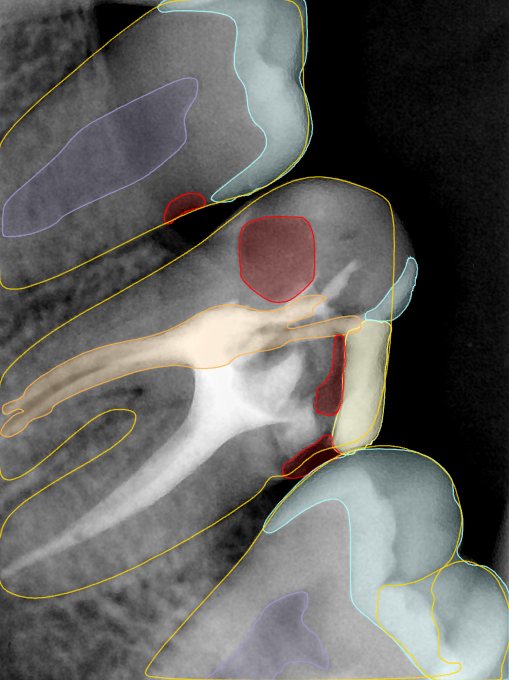

CR/DR 牙齿分割阶段记录

当前进展

- 完成了 CR/DR 牙齿相关分割训练

- 当前结果已经达到阶段预期,但仍有细节问题需要继续处理

相关测试

遇到的问题

- 训练过程中出现过 mask 下移问题

- 部分结果会出现 box 填充异常

- mask 边缘仍然有比较明显的锯齿感

参考

第二版算法问题测试

Updated: 2026-04-13(更新日期)

| 第一版 | 第二版 | 是否解决 | |

|---|---|---|---|

![]() | ![]() ![]() 边角识别有问题 龋齿识别不全 牙髓识别不全 | ![]() | 解决 |

![]() | ![]() 边角识别有问题 识别信息有误 自查(牙冠识别不全) | ![]() | 解决 |

![]() | ![]() ![]() 边角识别有误 大范围填充识别遗漏 | ![]() | 解决 |

![]() | ![]() 识别信息不全 | ![]() | 解决 |

![]() | ![]() ![]() 边角问题 牙胶识别不全 牙冠识别不全 | ![]() | 解决 |

![]() 换图片 | ![]() | ![]() 牙冠部分稍微白了一些就识别成小范围修补,部分判断异常 | 部分解决,修复类略敏感,牙冠部分稍微白了一些就识别成小范围修补,部分判断异常。 |

![]() | ![]() ![]() 牙冠识别不全 牙髓不全 根尖炎龋齿识别有误 | ![]() | 解决 |

![]() | ![]() | ![]() | 解决 |

![]() 换图片 | ![]() | ![]() | 解决 |

![]() | ![]() 牙冠识别有误 | ![]() | 解决 |

![]() 换图片 | ![]() ![]() 边角识别有误 | ![]() 修复类敏感 | 部分解决,图像过白,导致修复类判断异常。 |

![]() 换图片 | ![]() 牙冠识别不全 | ![]() 修复类敏感 | 部分解决,图像过白,导致修复类判断异常 |

结论:修复类出现了不鲁棒的情况,后续需要加入轮廓的扩充数据进行增强。